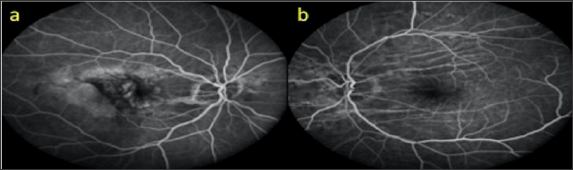

During the follow-up of an 81-year-old diabetic female, oblique choroid folds were detected outside the vascular arquades in both eyes. The VA was 8/10 in the right eye and 9/10 in the left eye. In biomicroscopic examination, posterior chamber intraocular lens was present in both eyes and IOPs were 13 mmHg bilaterally. In the fundus examination, moderate diabetic retinopathy findings and CFs were observed in both eyes. In OCT, RPE was observed to be fluctuating in the cross sections of the superior vasculature (Figure 9a & 9b). In FFA, CFs were observed in both eyes as light-dark lines with more obvious oblique outcrops than the upper main vascular arquade, and there were micro aneurysms occasionally due to diabetic retinopathy (Figure 10a & 10b).

Figure 10: FFA images (a,b).

An 81-year-old male who was followed up for age-related macular degeneration, horizontal-extending CFs were noted in the posterior pole of the left eye. VA was in the right eye at the level of hand movement perception and at the level of 7/10 in the left eye. Biomicroscopic examination revealed pseudophakia in both eyes. IOPs were 15 mmHg in both eyes. Inthefundusexamination, peripapillaryatrophy, macularscarand RPE detachmentareseen in therighteye (Figure 11a), withlight- darkbanding in theuppervascularquadrant, especially in thelefteye (Figure 11b). In the right eye, wide RPE detachment and sub retinal fluid were observed in the right eye (Figure 12a), while choroid and RPE wrinkles were observed in the left eye (Figure 12b). FFA revealed age-related neo vascular macular degeneration (Figure 13a). Horizontal extension of theCFstotheupperhalf of themaculaandveinligationaroundtheopticdiscwereobserved in the left eye (Figure 13b). Intravitreal ranibizumab therapy for the right eye of the patient was continued while left eye was taken in the direction of the CFs.

Figure 13: FFA images (a, b).